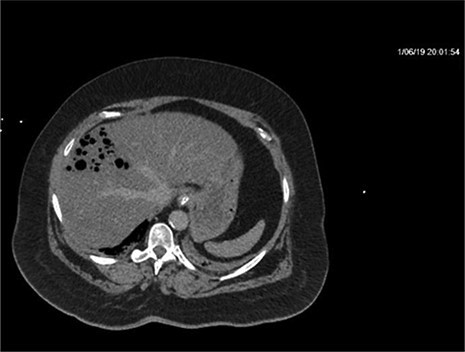

CT of the abdomen and pelvis with IV contrast was performed within 2 h of presentation. The scan showed “indeterminate, scattered ill-defined hypo-enhancing lesions in the liver with no acute etiology identified to explain the patient’s abdominal pain” (Figs 1, 3, 5). The remainder of the CT was unremarkable. Ultrasound (US) of the abdomen was negative. Because the CT and US did not identify an etiology for the patient’s abdominal pain, the working diagnosis at that time was an intestinal obstructive process.

CT with IV contrast taken at 0633 which shows ill defined, hypo-enhanced lesions of the liver.